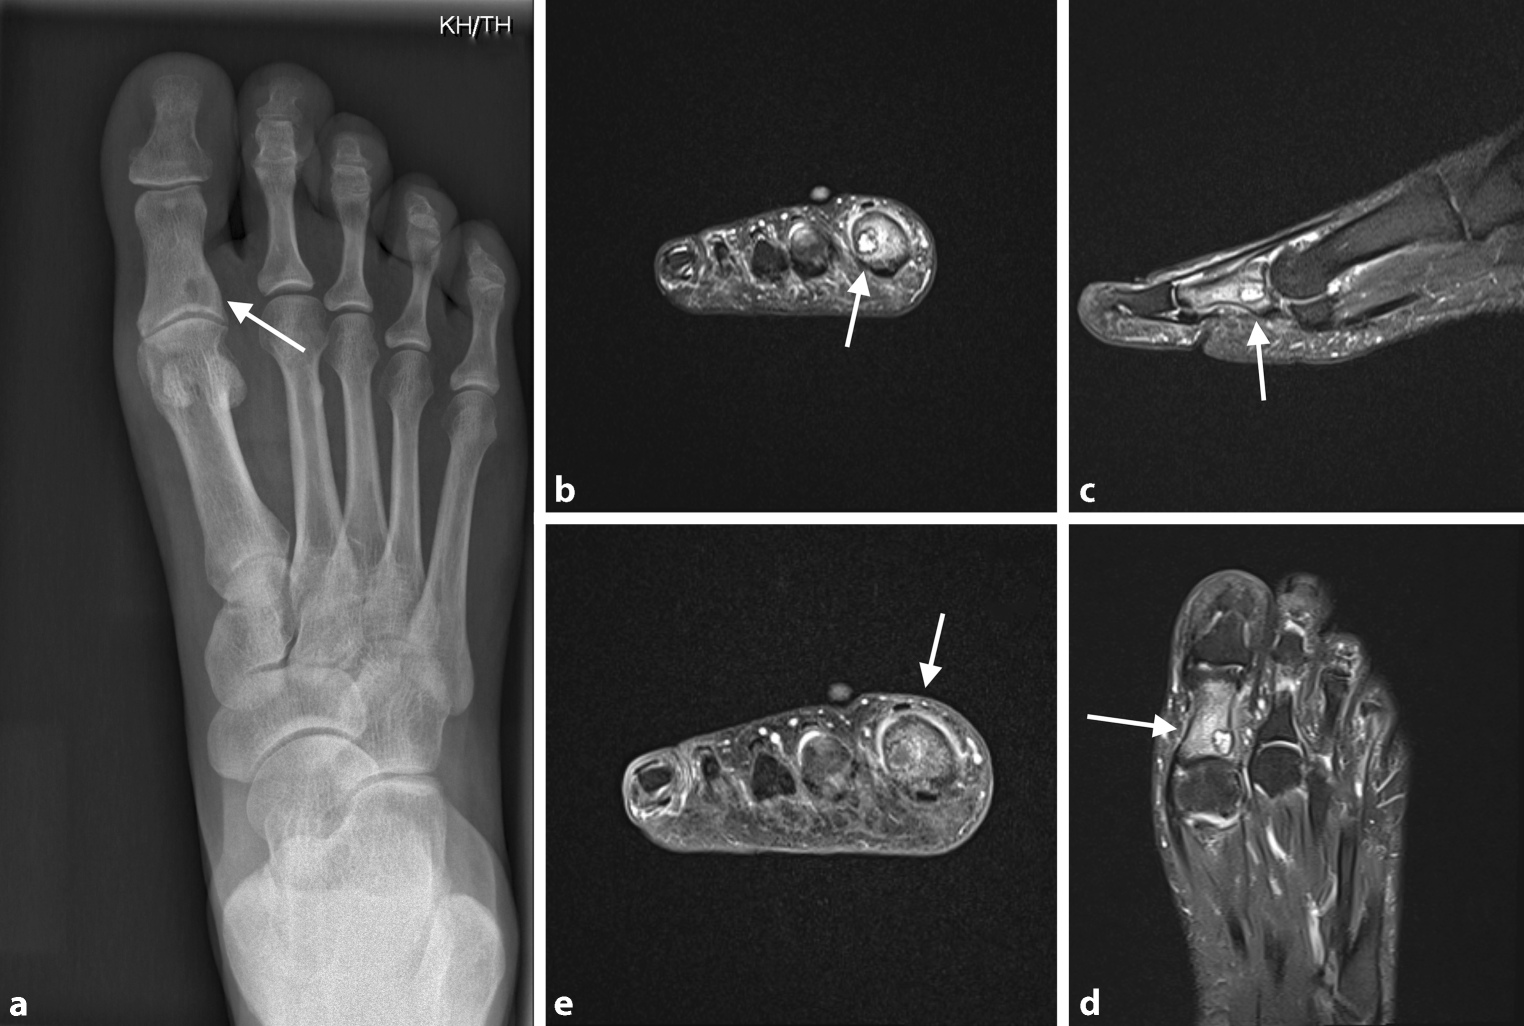

Fig. 4

a 55-year-old female patient with osteoid osteoma of the 1st proximal phalanx of the right foot. X‑ray with lytic lesion and cortical thickening at the medial aspect of the base of the 1st proximal phalanx (arrows pointing at the regions of interest). be MRI scans showing well-circumscribed sclerotic lesion of 6 mm in size with extensive bone edema. Minor synovial reactive effusion at the 1st metatarsophalangeal joint (b T2 Turbo spin echo (TSE) fatsat (FS); c ,d T2 FS; e T1 TSE + Contrast Agent; arrows pointing at the regions of interest)